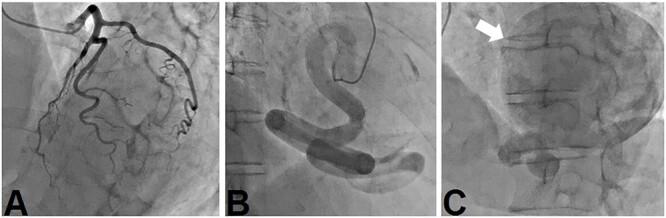

A rare case of giant coronary artery ectasia associated with coronary artery aneurysm was recognized. A 69-year-old woman presented with an ischemic electrocardiogram changes during a medical check-up. Coronary computed tomography angiography showed right coronary artery (RCA) ectasia associated with a giant aneurysm originating from the distal RCA. She was asymptomatic and exhibited no risk factors, including Kawasaki disease, hypertension, diabetes mellitus or family history. The patient underwent surgery for giant coronary aneurysms to prevent rupture. The aneurysm was on the peripheral side of the right coronary artery; hence, coronary artery bypass was not performed. The patient's postoperative course was uneventful. Histopathological examination of the aneurysm revealed degeneration due to atherosclerosis. She was prescribed warfarin and aspirin for thrombus prevention.

一例罕见的巨大冠状动脉扩张合并冠状动脉瘤被确诊。一名69岁女性在体检时出现缺血性心电图改变。冠状动脉计算机断层扫描血管造影显示右冠状动脉(RCA)扩张,伴有一个起源于RCA远端的巨大动脉瘤。她没有症状,也没有包括川崎病、高血压、糖尿病或家族史在内的危险因素。患者接受了巨大冠状动脉瘤手术以预防破裂。动脉瘤位于右冠状动脉外周侧;因此,未进行冠状动脉搭桥术。患者术后恢复顺利。动脉瘤的组织病理学检查显示为动脉粥样硬化性退变。她被开了华法林和阿司匹林以预防血栓形成。